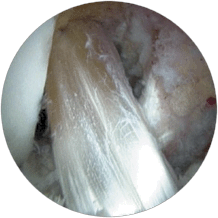

Arthroscopic Knee Surgery:

Mr Pang has performed numerous arthroscopic (key-hole) knee surgery including meniscal repair or resection, ACL (anterior cruciate ligament) reconstuction and patello-femoral reconstruction for instability. He will discuss with you the indications for surgery, the rehabilitation protocol and the expected outcome.